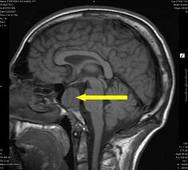

Рентгенография и компьютерная томография черепа помогают в постановке диагноза.

На рентгене видно расширение турецкого седла, где расположен гипофиз.

На компьютерных томограммах визуализируется опухоль.

В сомнительных случаях проводят исследования с помощью ядерно-магнитного резонанса (ЯМР).

На рентгене видно расширение турецкого седла – костного образования, в котором находится гипофиз.

На компьютерных томограммах визуализируется опухоль различного размера и формы, изменения в гипофизе или гипоталамусе четче проявляются при использовании контрастных веществ.

В сложных случаях применяются исследования с помощью ядерно-магнитного резонанса (ЯМР).